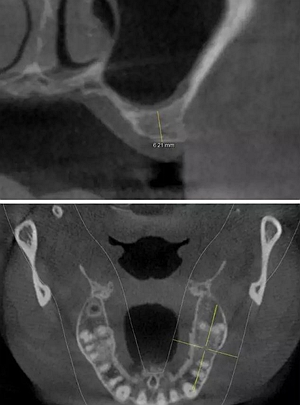

術(shù)后CBCT

提升時相關(guān)步驟可參考下面圖片

可見在完善的檢查和適當(dāng)?shù)墓ぞ哌x擇下可順利完成較復(fù)雜的上頜竇手術(shù)。